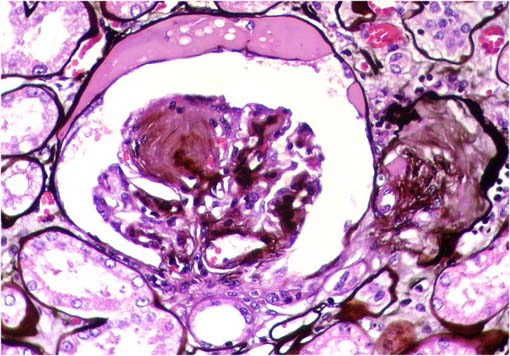

Figura 2.

Tricrómico de Masson, X400.